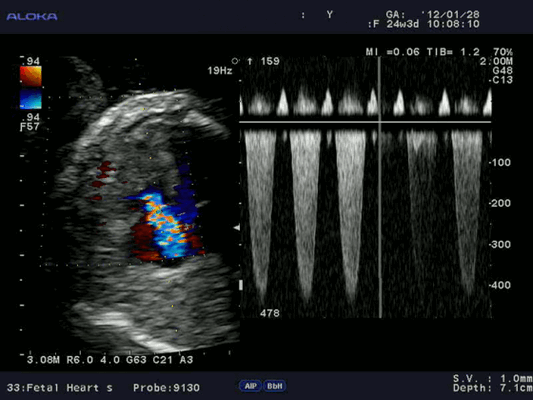

Измерение скоростных характеристик позволяет оценить:

Допплерэхокардиография позволяет измерить все вышеперечисленные параметры, которые очень важны при оценке детской сердечной патологии (врожденные пороки) без использования инвазивной процедуры — катетеризации сердца. Помимо этого, назначение эхокардиографии с допплеровским анализом ребенку не несет никакой угрозы по сравнению с компьютерной томографией, где используется рентгеновское излучение.